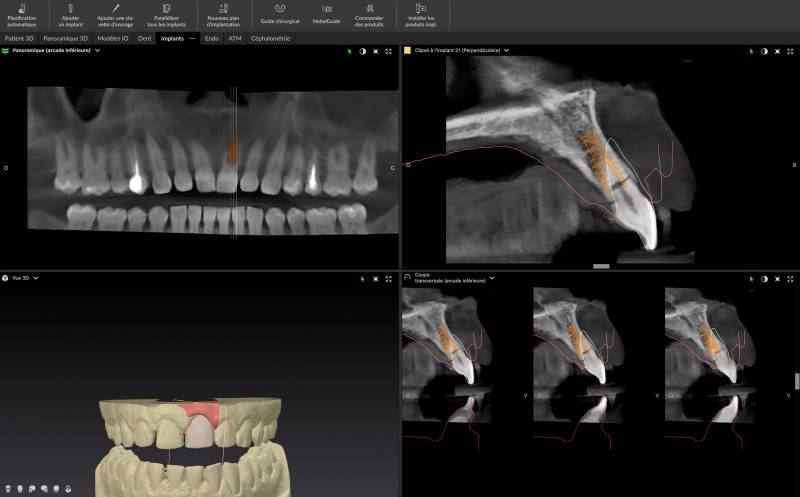

Chaque traitement implantaire à Marseille repose sur un diagnostic complet, une planification 3D à l’aide d’un scanner Cone Beam et le choix rigoureux du systèmes implantaires de référence (Nobel Biocare, Biotech Dental), afin d’offrir une solution fiable, sécurisée et pérenne, parfaitement adaptée à chaque situation clinique.

Bilan implantaire à Marseille : analyse 3D Cone Beam et planification précise avant la pose d’un implant dentaire.

Le bilan implantaire à Marseille – Un diagnostic essentiel pour assurer le succès de votre implant dentaire

Le bilan implantaire est une étape essentielle avant toute pose d’implant dentaire à Marseille. Cette consultation permet d’établir un diagnostic précis, de définir le plan de traitement, la planifi...

Bilan pré-implantaire à Marseille 13009

Les étapes d’un bilan pré-implantaire par notre cabinet dentaire Maupassant à Marseille

L’implantologie ne s’improvise pas.Pour que la pose de votre implant dentaire présente le meilleur taux de succès et de pérennité, un bilan...